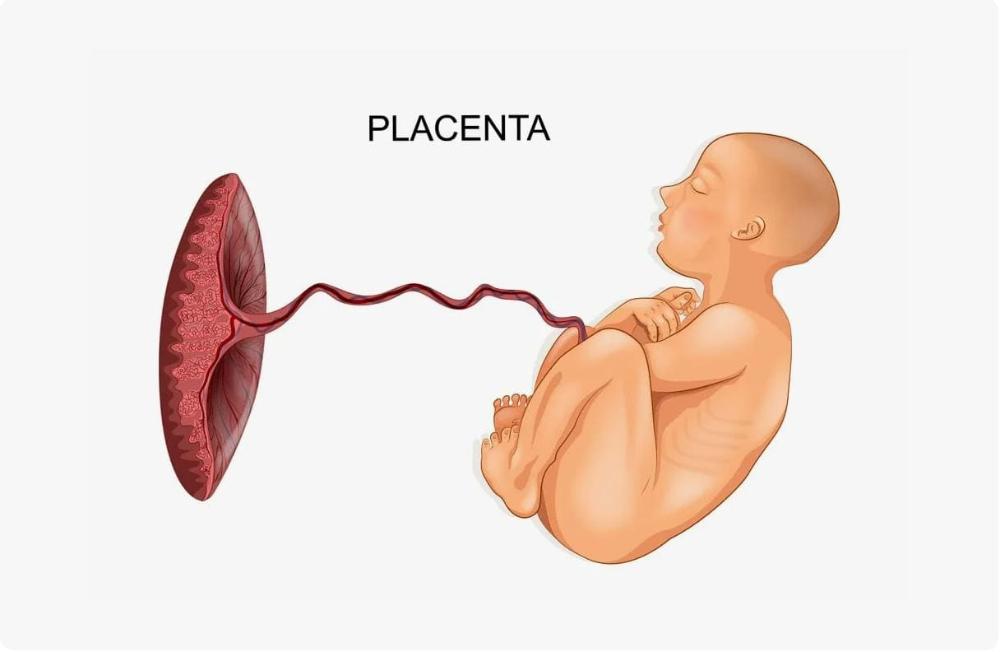

Околоплодный пузырь и плацента: структура и функции